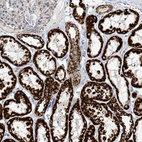

Immunohistochemical staining of human kidney, liver, pancreas and testis using Anti-SUCLG2 antibody HPA051998 (A) shows similar protein distribution across tissues to independent antibody HPA046705 (B).